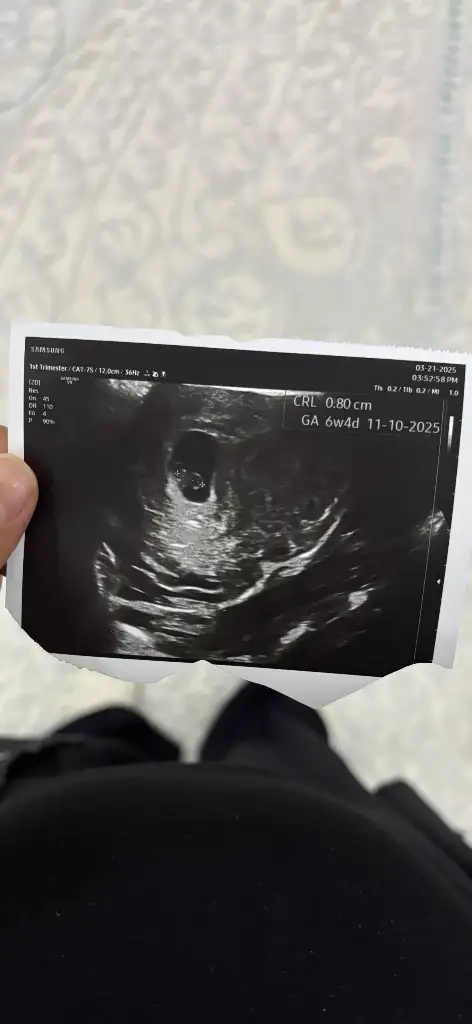

Yaa bizede bakabilir misiniz çok merak ediyorum görsellerde ilk görsel 10+4 diğer görseller 6+4 haftalık :)Pek iyi anlamıyorum ama nub teorisi fotolarına baktığım kadarıyla kız gibi görünüyor

Banada bakabilir miisniz görsel olarak yorumlara ekledim :) ilk görsel 10+4 diğer görseller 6+4 haftalıkken karından ultrasonla bakıldı

benimkine de bakın bu nedir iki bacak arası görünüyorVajinal ultrasonla bakıldıysa bebeğiniz kız olabilir